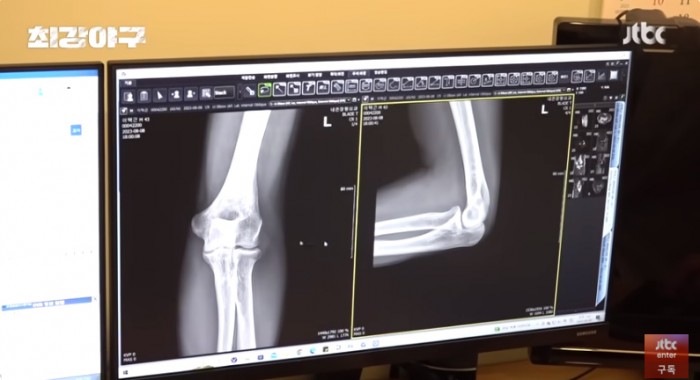

이택근이 팔 통증이 너무 심해 수술 후 타격까지 1년이 걸리는 수술을 했는데..

자신의 자리는 자신이 만들어가는 것이라는 걸 보여준 이택근의 간절함